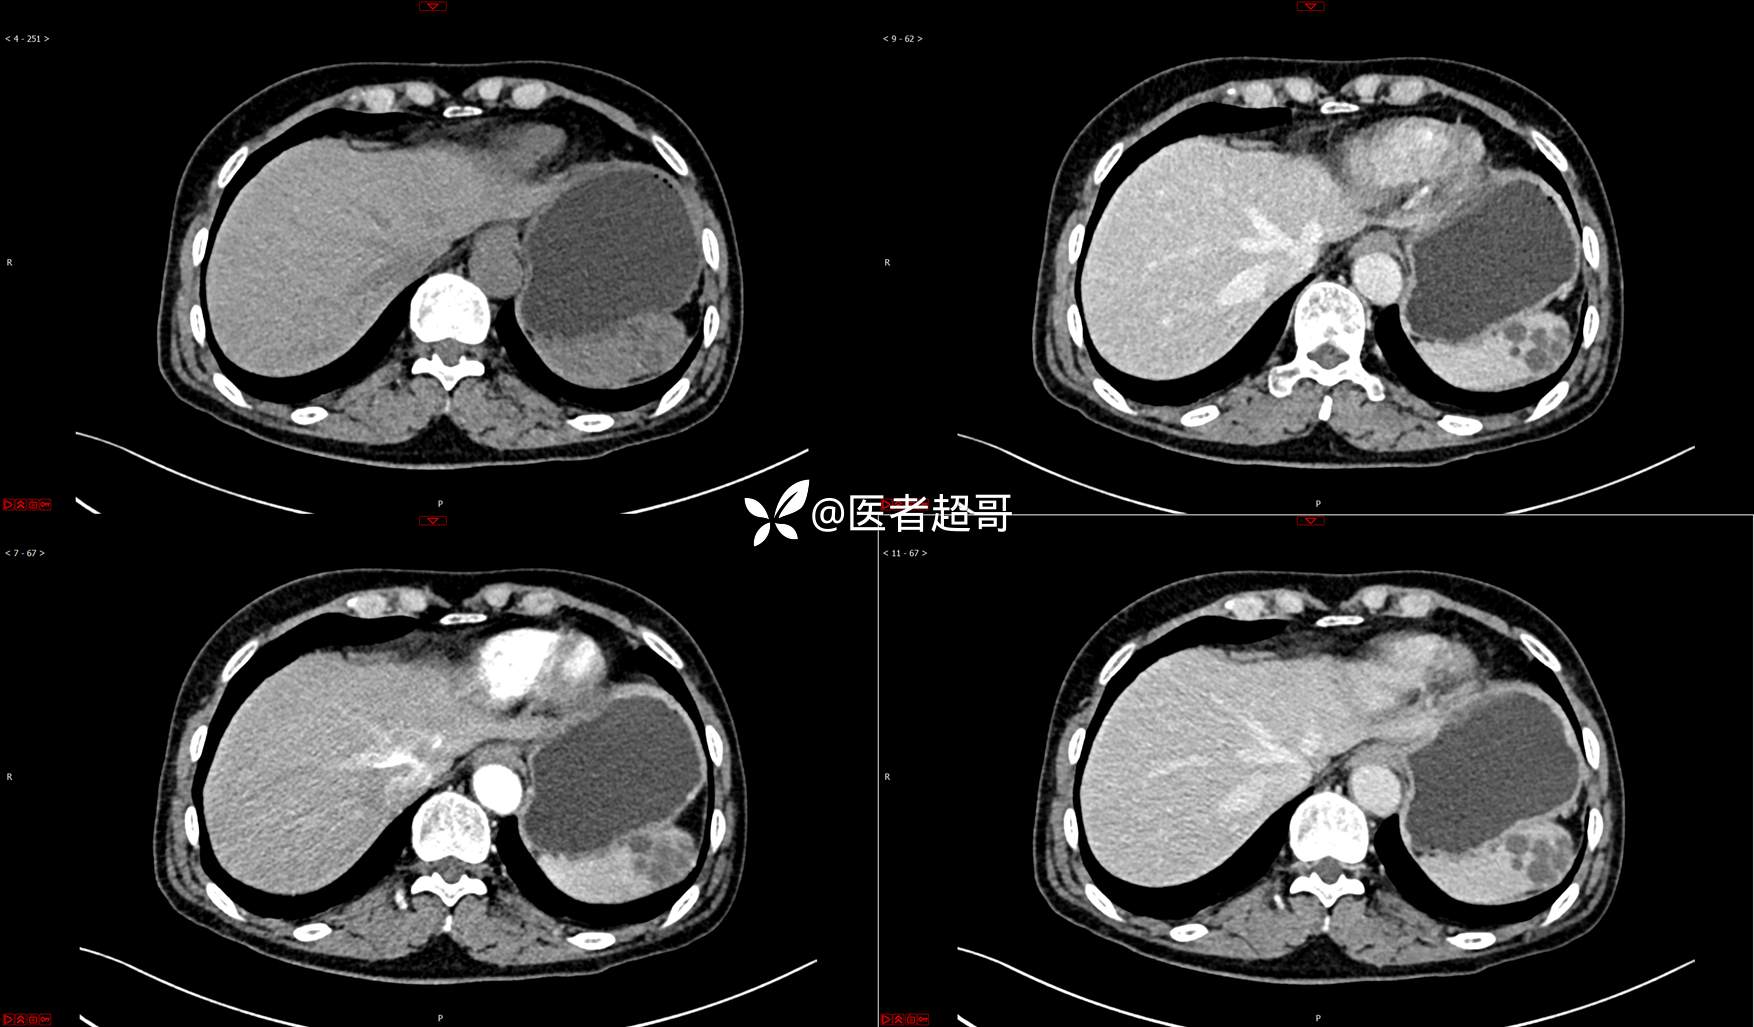

【影诊笔记739】脾脏囊性占位,查体偶发,请赏析,有病理!

女,6岁 0201215 02

主 诉:查体发现脾脏囊性占位4年。

现病史:患者4年前于人民医院查体时发现脾脏囊性占位。-04-20到我院复查,行上腹平扫+强化CT示:肝囊肿,脾脏囊实性占位,囊腺瘤?当时无明显症状,未行任何治疗。4个月前无明显原因及诱因开始偶尔出现左上腹疼痛,为隐痛,伴腰部放射痛,无腹胀、腹泻,无恶心、呕吐,无发热、畏寒、全身乏力,无胸痛、胸闷等其它不适。在外未行特殊治疗,今为求进一步诊治来我院就诊,行腹部彩超(肝、胆、胰、脾、肾)示:脾脏房囊性肿物。门诊以“脾占位性病变”收入院。发病以来,患者神志清楚,精神可,饮食可,睡眠欠佳,大小便正常,近期体重无明显变化。